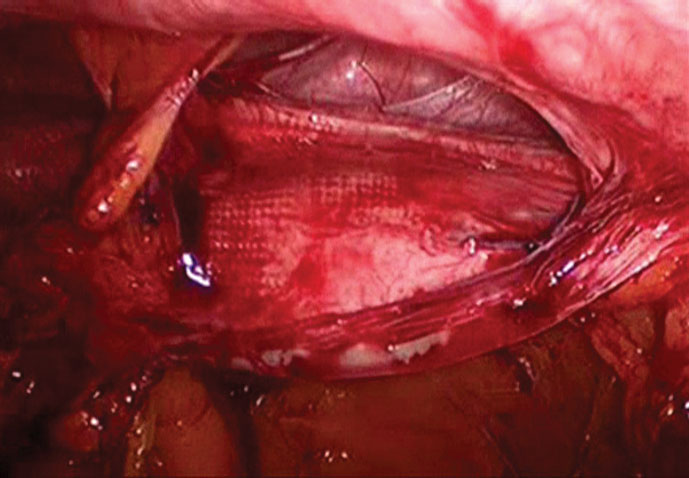

Video 1 demonstrates the size of a pristine mesh placed over the left groin in the extraperitoneal space. This covers the entire myopectineal orifice fairly well.

In the patient with a right groin inguinal hernia recurrence, the mesh (similar in type to the dual-layered heavyweight polypropylene shown in the previous video) has contracted about 90% from its original size. (Figure 1)

The patient in Video 4 had postoperative groin pain. The mesh can be seen contracted inferior to the tacks, which no longer penetrate the contracted mesh. (Figure 2)